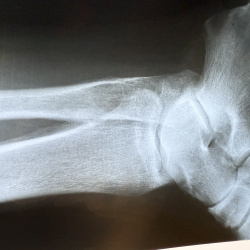

Здравствуйте, пациент 78 лет. 2 мес назад, падение на руку, в травму не обращался. Сейчас есть сгибательная контрактура в ЛС и пронация предплечья, кисть провисшая, пальцы самостоятельно не...